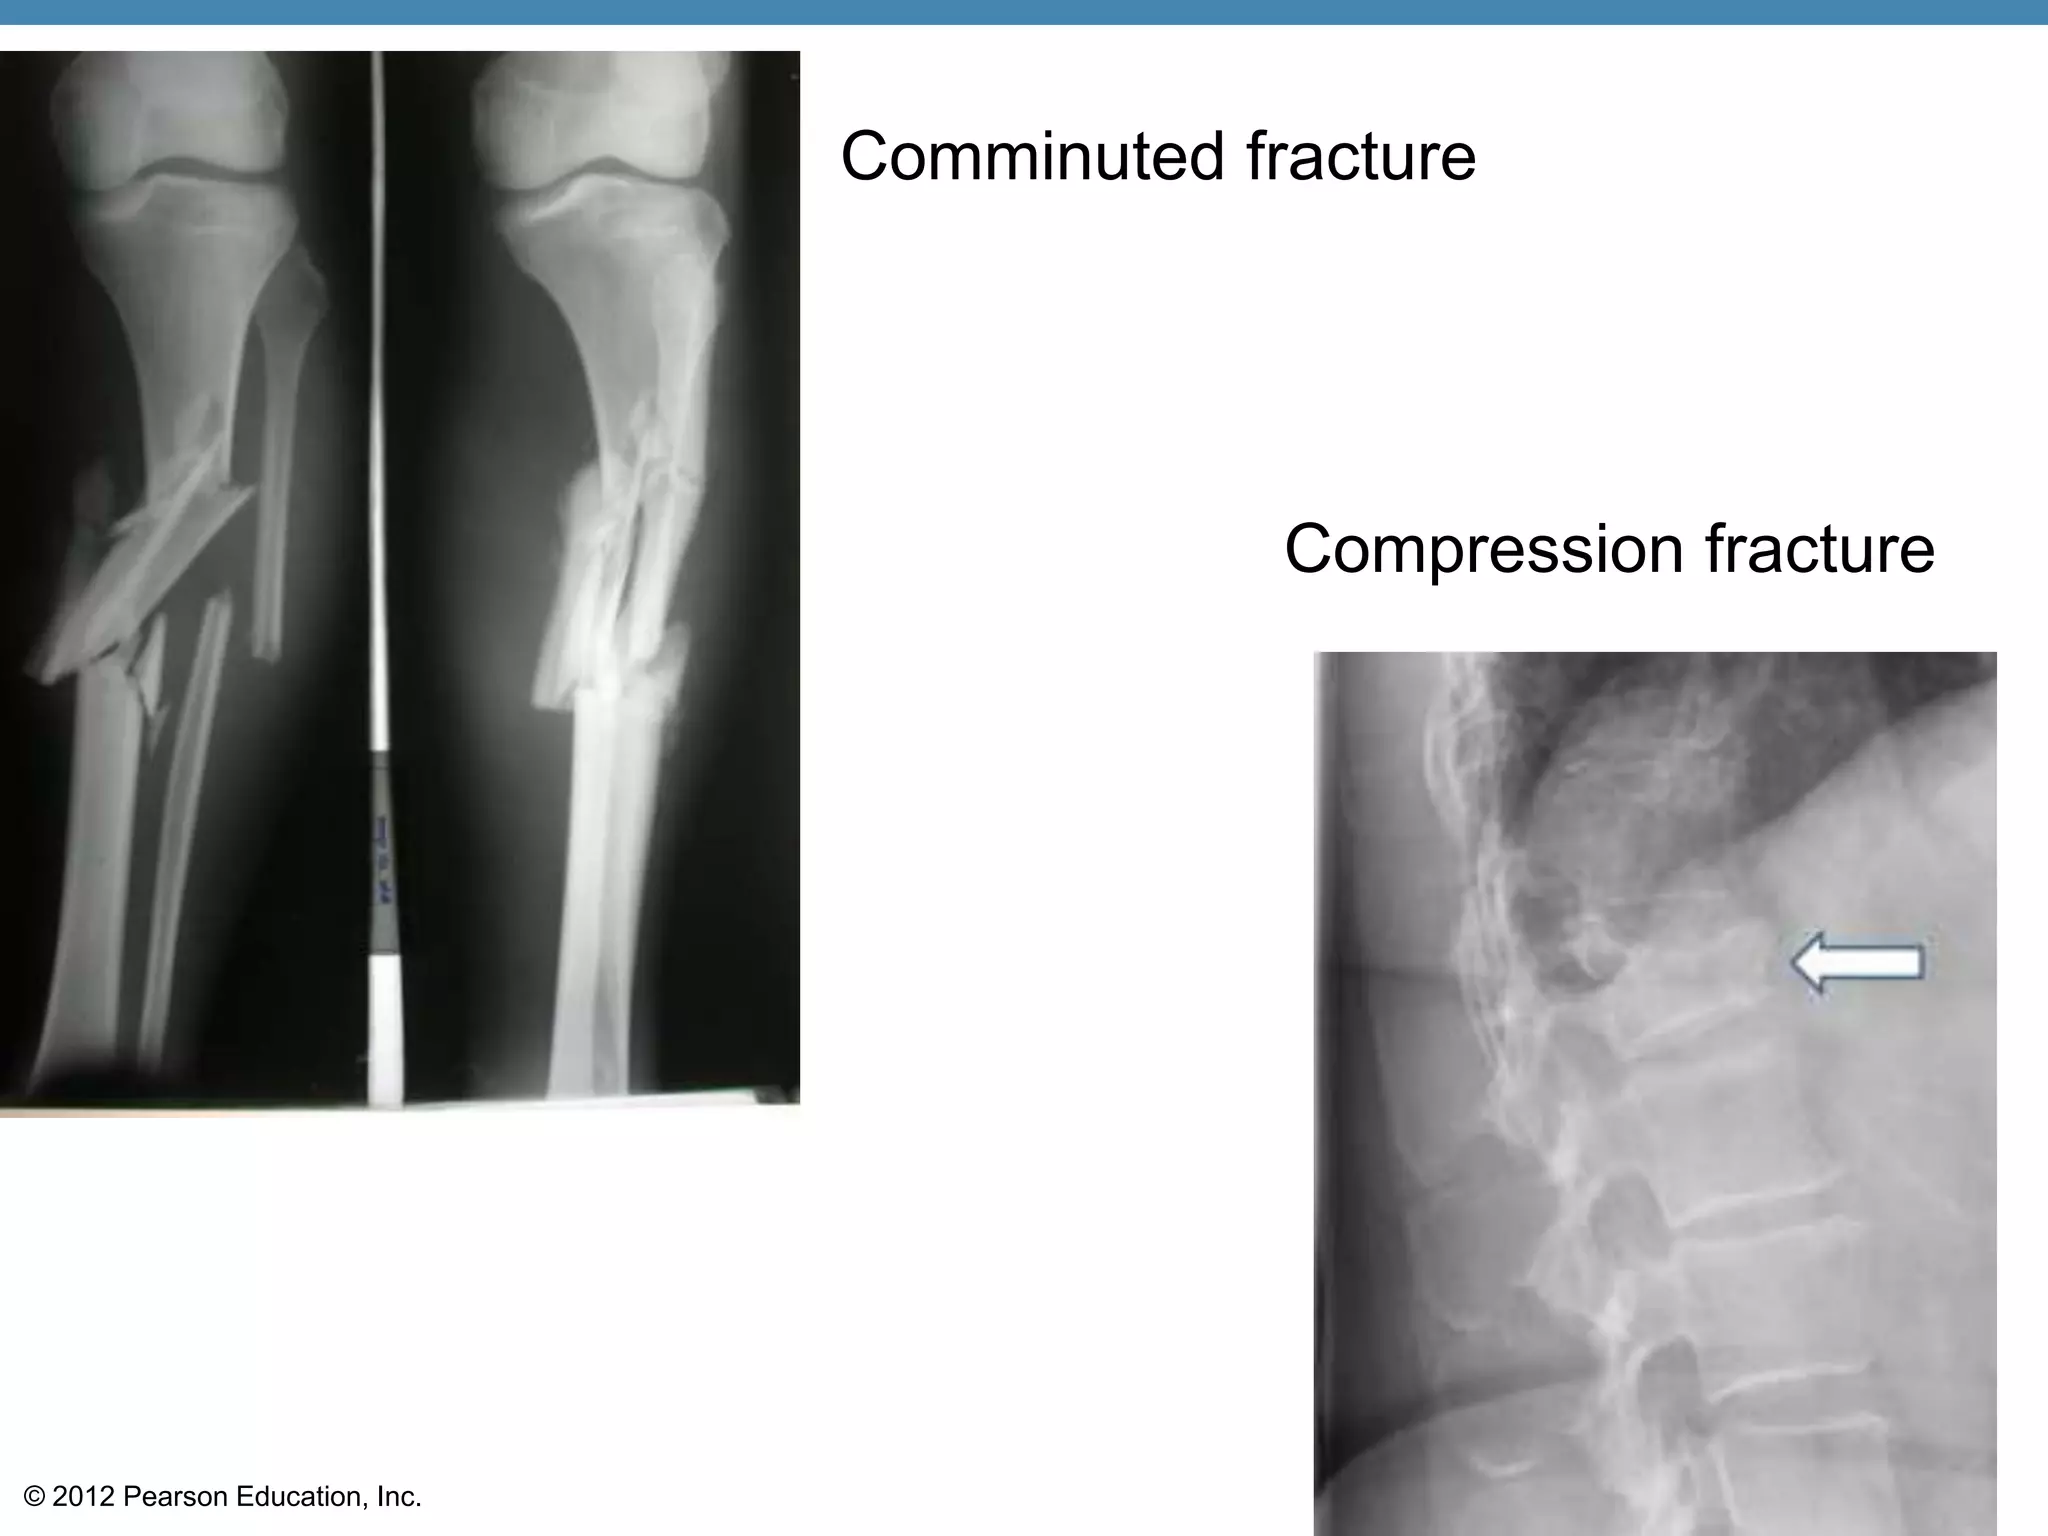

Bone Fractures

•Fracture—break in a bone

•Types of bone fractures

•Closed (simple) fracture—break that does

not penetrate the skin

•Compound fracture—broken bone

penetrates through the skin

•Bone fractures are treated by reduction and

immobilization

Common Types of Fractures

•Comminuted—bone breaks into many

fragments                    Setting a bone:

•Compression—bone is crushed

Comminuted fracture

Compression fracture